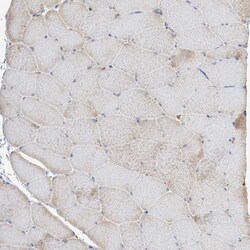

| Immunohistochemistry (Paraffin), Western Blot, Immunocytochemistry | |